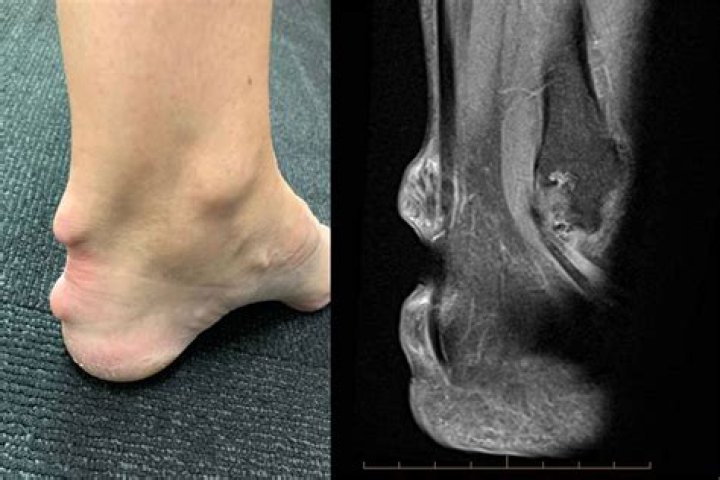

How do you know if you have plant thorn arthritis?

The diagnosis of plant thorn arthritis is made by detection of a piece of thorn within the joint by imaging tests or surgical removal and identification of the thorn fragments. The involved joint may be swollen, painful, reddened, stiff, and may have a reduced range of motion.

Plant thorn synovitis, also known as plant thorn arthritis, is a rare and commonly overlooked cause of arthritic disease. This disease is attributed to a granulomatous inflammatory response to retained plant thorn fragments following a puncturing plant thorn injury.